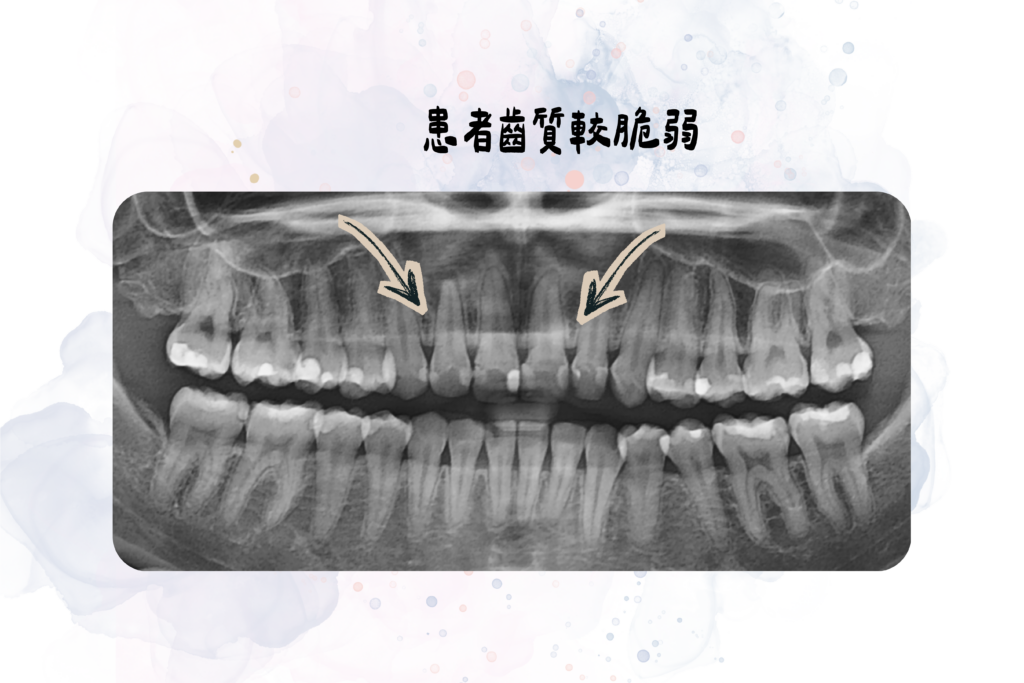

在初步評估過程中,郭東溫醫師發現患者前牙過去已有多顆補過牙,齒質結構相對脆弱。

患者x光片